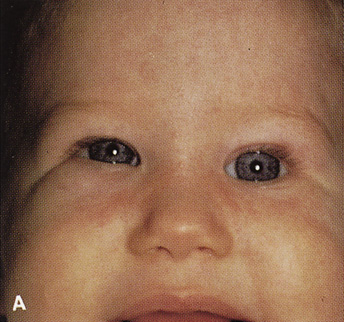

Fig. 14. A,B. Large intraorbital lymphangioma causing proptosis and optic nerve compression

in a 2-year-old child. C. View of the left orbit from above after removal of the frontal bone flap, including

the supraorbital rim and orbital roof. An extensive exposure

of the entire superior and lateral orbit is afforded. The levator

and superior rectus complex is being retracted laterally with a muscle

hook, whereas the Freer elevator retracts the superior oblique muscle

medially. The frontal nerve can be seen running from posterior to anterior

over the superior orbit. The orbital mass is exposed in this fashion. D. The fronto-orbital bone flap is wired back in place after completion of

the procedure. E. Postoperative appearance of the patient. F. The postoperative CT scan shows complete removal of the lymphangioma. This

large and diffuse lesion would have been difficult to remove with